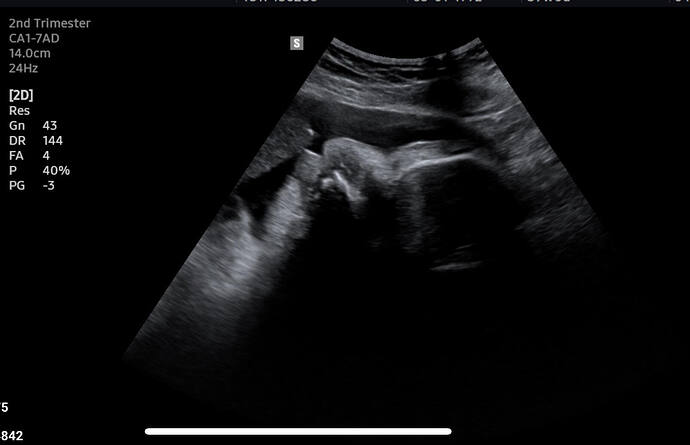

Hatta son aydaki ultrasonu şuydu hatta ultrasonu çeken bile burnu ne büyük diyip moralimi bozmuştu